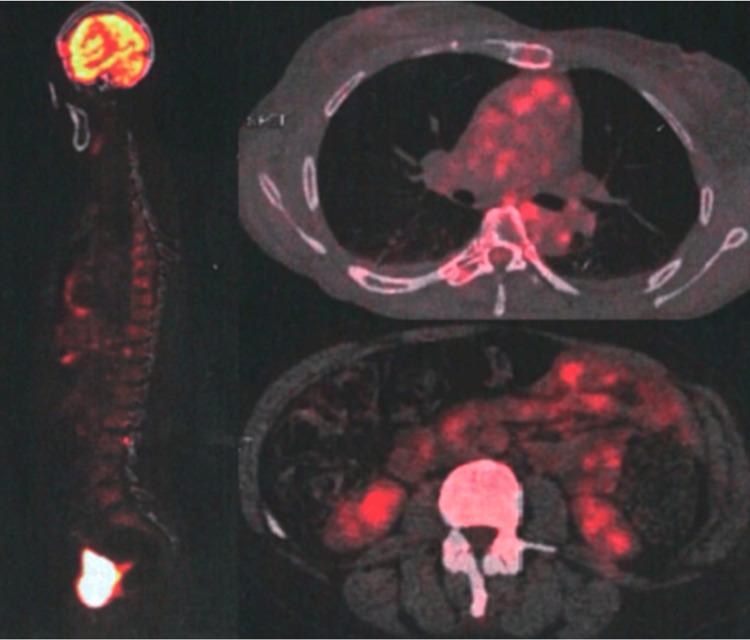

Stiff person syndrome (SPS) is a progressive autoimmune disorder characterized by muscle rigidity, frequent falls, and spasms, affecting primarily women. Recent advances have linked SPS to specific antibodies, such as anti-glutamic acid decarboxylase (GAD)-65, but effective treatments remain elusive. We report the case of a 53-year-old female who developed chronic lower back pain, tingling paresthesias, and progressive rigidity in the lower limbs. Electromyographic examination revealed muscle spasms and co-contractions, along with severe rigidity and reactive spasms upon touch. Imaging studies showed a polymyomatous uterus and no hypermetabolic lesions. She was diagnosed with stiff person syndrome with positive anti-GAD65 autoantibodies. Patient was treated with methylprednisolone, oral corticosteroids, gabapentin, baclofen, alprazolam, immunoglobulins, and rituximab, leading to moderate improvement in her condition. This case report aims to highlight the association between SPS and anti-GAD65 autoantibodies, emphasizing the importance of early diagnosis and comprehensive management.

僵人综合征(SPS)是一种进行性自身免疫性疾病,其特征为肌肉僵硬、频繁跌倒和痉挛,主要影响女性。最近的研究进展将SPS与特定抗体联系起来,如抗谷氨酸脱羧酶(GAD)-65,但有效的治疗方法仍然难以捉摸。我们报告了一例53岁女性病例,该患者出现慢性下背部疼痛、刺痛感觉异常以及下肢进行性僵硬。肌电图检查显示肌肉痉挛和共同收缩,触摸时伴有严重僵硬和反应性痉挛。影像学研究显示子宫多发肌瘤,无高代谢病变。她被诊断为抗GAD65自身抗体阳性的僵人综合征。患者接受了甲泼尼龙、口服糖皮质激素、加巴喷丁、巴氯芬、阿普唑仑、免疫球蛋白和利妥昔单抗治疗,病情有中度改善。本病例报告旨在强调SPS与抗GAD65自身抗体之间的关联,强调早期诊断和综合管理的重要性。